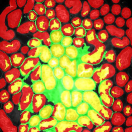

The first row in Figure 3 displays an original microscopy image (), its inhomogeneity corrected version (), and manually delineated groundtruth (), respectively. For brevity we have omitted the superscript in the notation. The second row shows segmentation results of various 3D methods such as 3D region-based active contours [10] (3Dac), 3D active contours with inhomogeneity correction [11] (3DacIC), and 3D Squassh presented in [12] (3Dsquassh). Similarly, the third row portrays various segmentation methods particularly designed for tubular structure segmentation such as ellipse fitting method presented in [15] (Ellipse Fitting), the Jelly filling method in [20] (Jelly Filling), and tubule segmentation using steerable filter [21] (Steerable Filter). Finally, the last row shows segmentation results of our proposed CNN architecture without inhomogeneity correction [27] (2DCNN) and with inhomogeneity correction (2DCNNIC).

For visual comparison we highlighted groundtruth regions in red, segmented tubule regions in green, and background in black. As observed in Figure 3, our proposed method appeared to perform better than the other six methods shown in the second and third rows by distinguishing tubules and was similar performance to 2DCNN. Note that since some methods such as Ellipse Fitting, Jelly Filling, and Steerable Filter only segmented boundaries of tubule structures, tubule interiors were filled in order to perform a fair comparison using connected components with a -neighborhood systems. Also, based on the assumption that tubule regions should contain lumen, if a filled region contained lumen pixel, the region was identified as a tubule region. However, if a filled region did not contain any lumen pixels, the region was considered as a background region.

The segmentation results shown in the second row generally missed many tubule regions. More specifically, 3Dac and 3Dsquassh could not capture the tubular structures but captured some in the center regions due to the intensity inhomogeneity of microscopy images. 3DacIC failed to segment tubular structures but captured multiple lumens inside tubules as well as some tubule boundaries. In contrast, the segmentation results displayed in the third row showed falsely detected tubules. The main reason is that these tubule segmentation methods focused only on detecting boundaries of tubular structures. In particular, due to weak/blurry edges of fluorescence microscopy images, many boundaries were not continuous causing the filling operation to overflow from one tubule to another or to the background regions. The segmentation results using the CNN generally successfully segmented and identified each tubule region.

Figure 4 provides an alternative way to show the segmentation results. In particular, yellow regions correspond to true positives which are pixel locations that are identified as tubules in both the groundtruth and segmentation results. Green regions correspond to false positives which are pixel locations that are identified as background in groundtruth but tubules in segmentation results. Similarly, red pixels correspond to false negatives, namely pixel locations identified as tubules in the groundtruth but background in segmentation results, and black pixel regions correspond to true negative that are identified as background in both groundtruth and segmentation results. The green regions indicate Type-I error (false alarm) regions and the red regions represent Type-II error (miss) regions. As observed from Figure 4, the segmentation results in the first row contained large red regions which mean large regions of tubules were missed. Conversely, the segmentation results shown in the second row contained many green regions indicating many background regions were falsely segmented as tubule regions. In contrast, the segmentation results in the third row had reasonably small green regions and red regions which indicate that the deep learning based segmentation results had higher pixel accuracy with relatively low Type-I and Type-II errors.